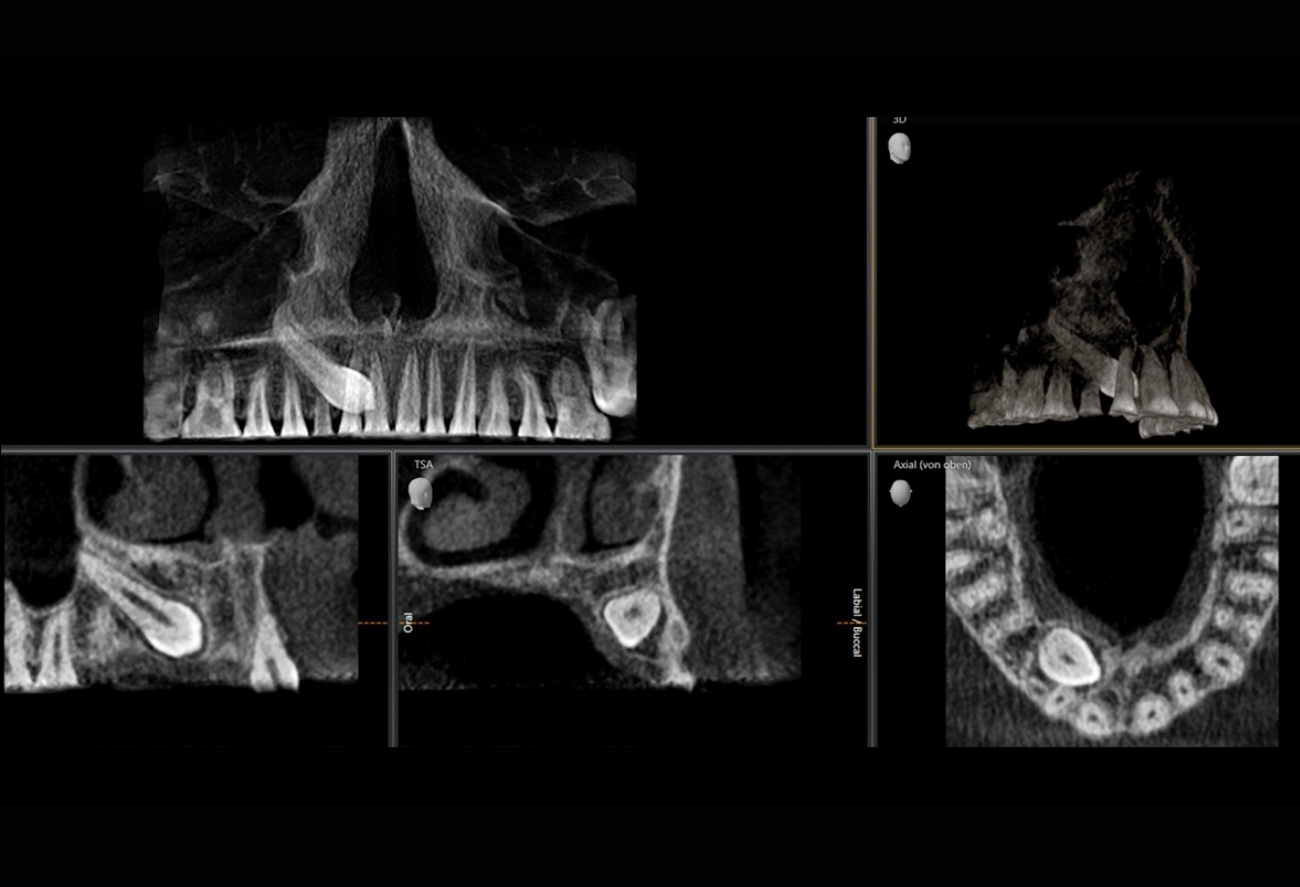

Приклади 3D-зображень: